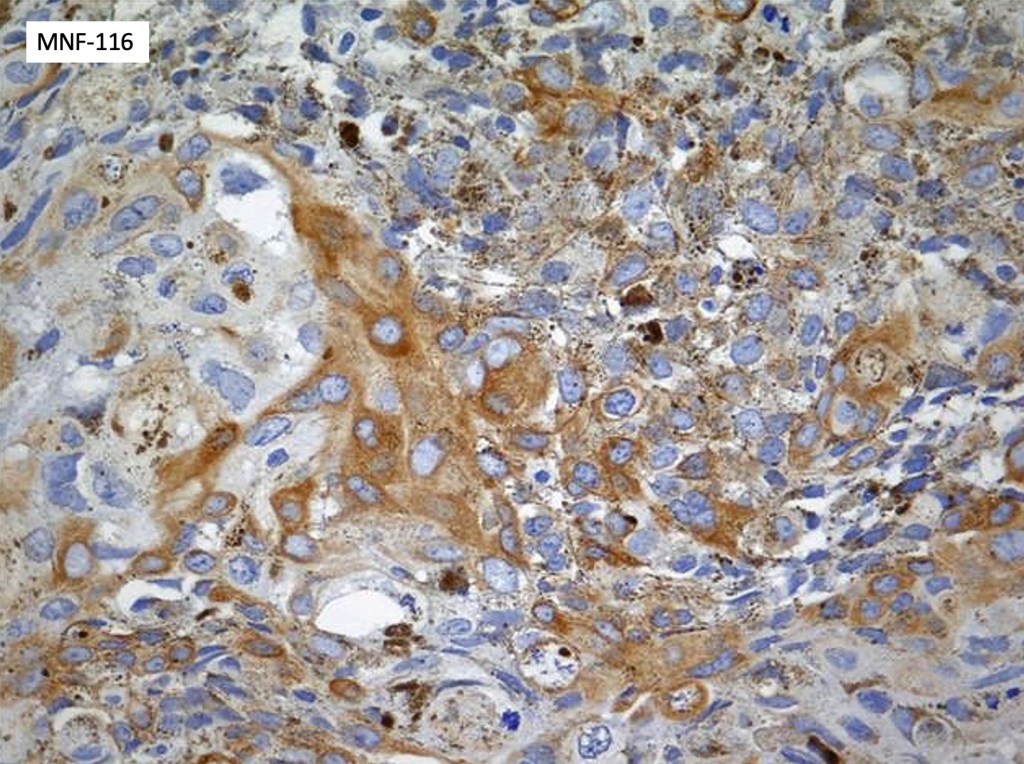

•Heavily pigmented dendritic +/- epithelioid melanocytes

•Basaloid cells show nuclear & cytoplasmic expression of β-catenin

•Dendritic population is enhanced with a Masson Fontana stain